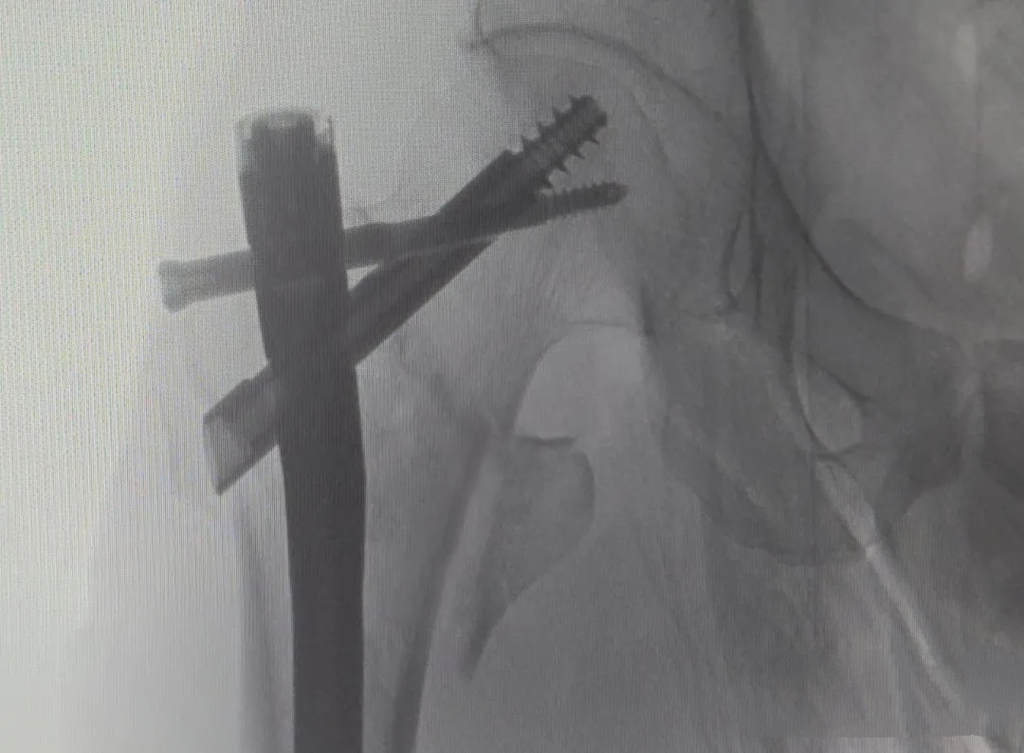

术后DR影像图

据了解,PFBN(股骨近端仿生髓内钉)系统是国内先进的股骨近端骨折内固定技术,其设计基于人体生物力学仿生原理,创新构建“三角支撑”结构。相较于传统PFNA(股骨近端防旋髓内钉),PFBN在抗旋转、抗内翻及整体稳定性方面具有显著优势,能有效避免螺旋刀片切割股骨头或退钉风险,尤其适用于高龄、骨质疏松及复杂类型骨折患者。